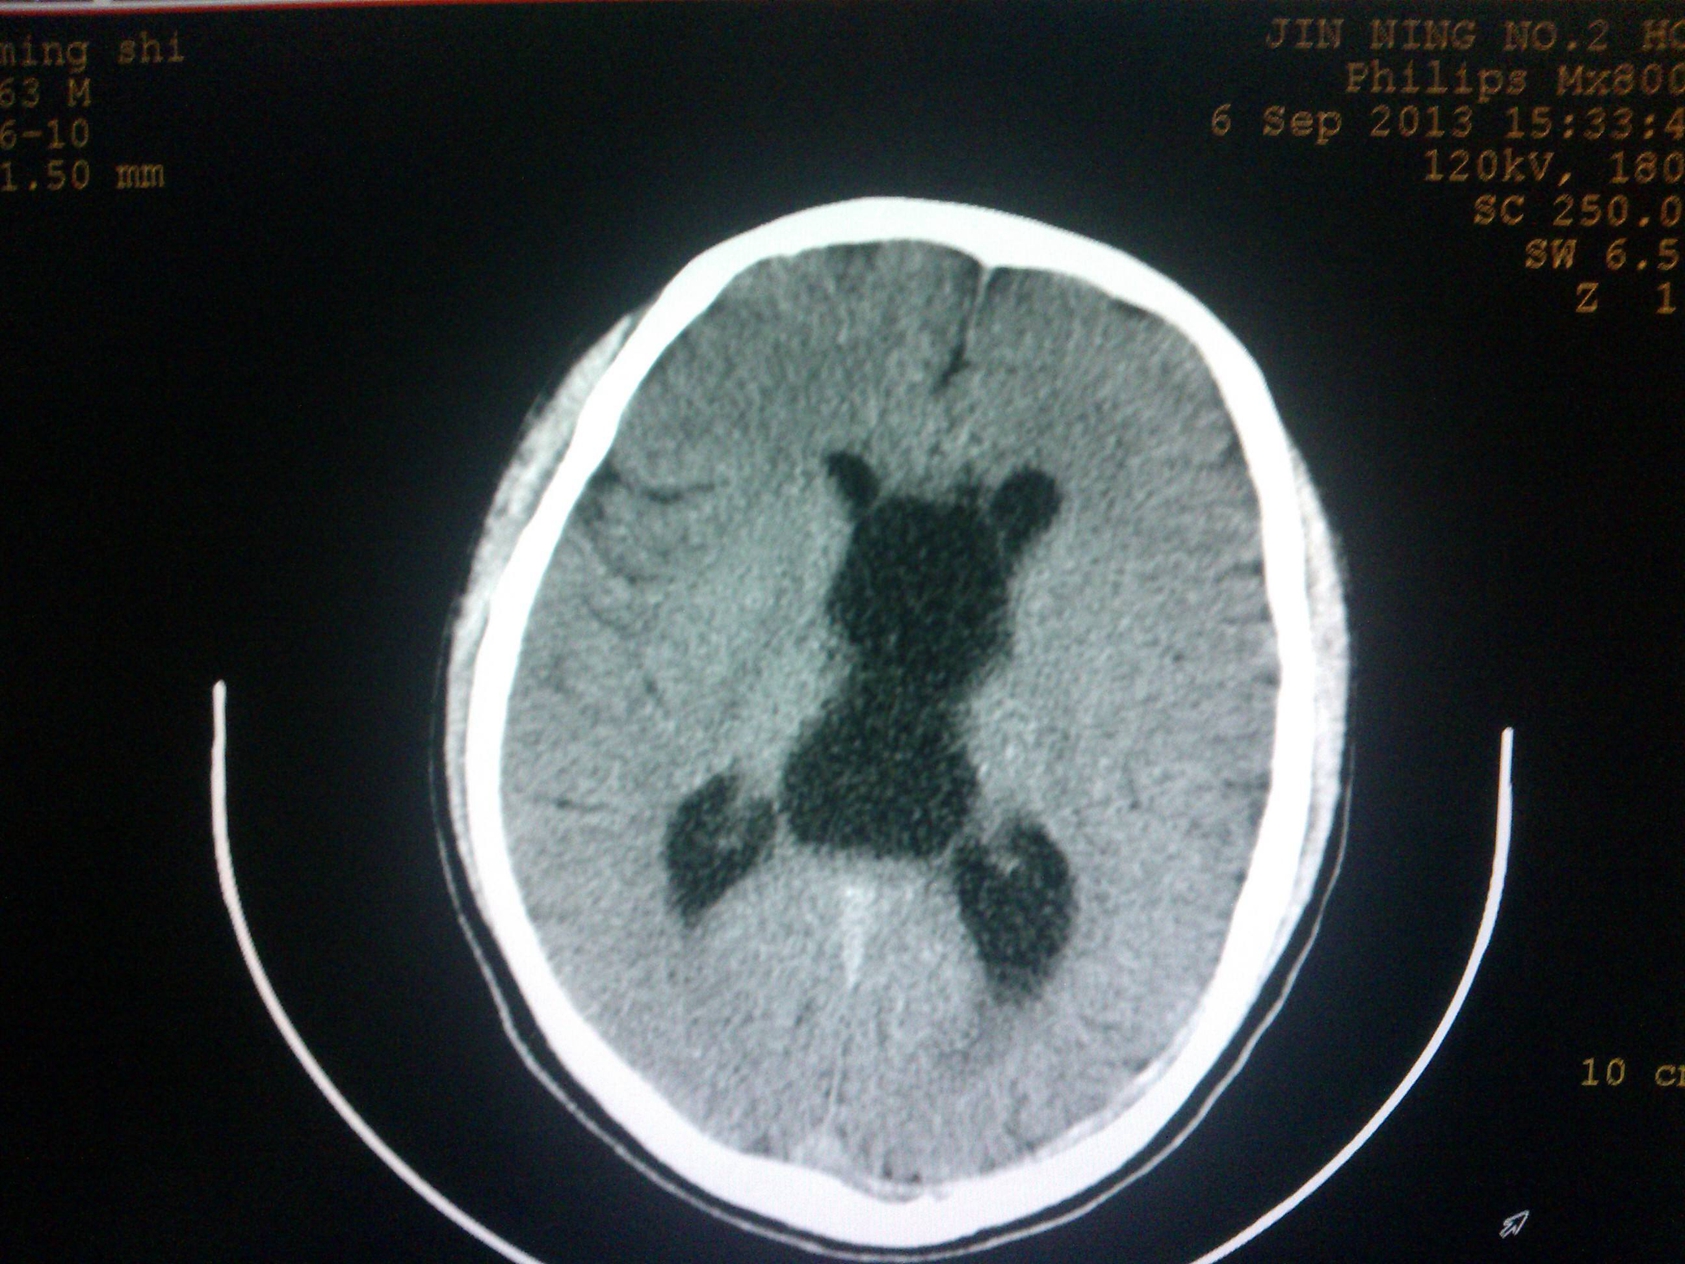

1.下列哪種方法為顱腦疾病診斷的基本方法: ( )

A.腦室造影 B.計(jì)算機(jī)體層 C.頭顱平片 D.醫(yī)學(xué)影像 E.腦血管造影